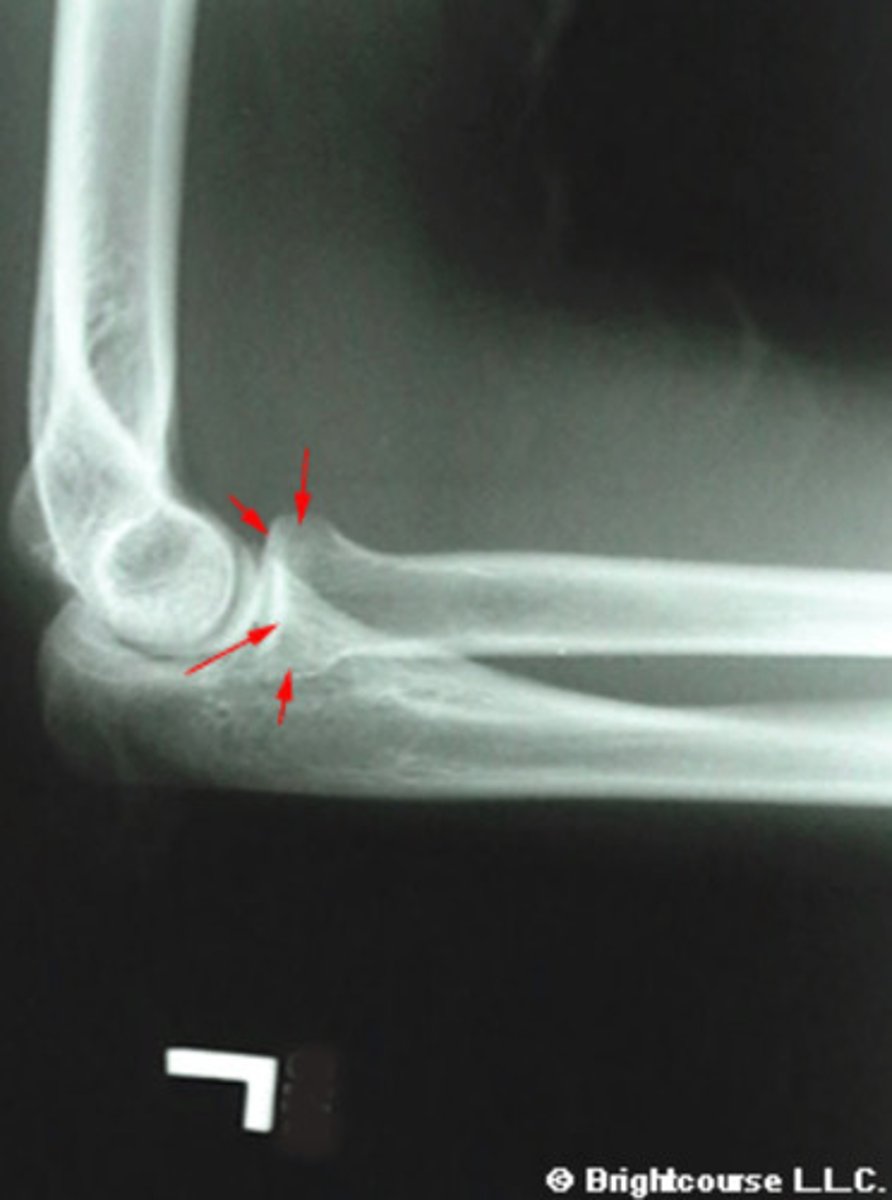

What is being pointed out by the arrows in this image?

What structure is being pointed out by the arrows?